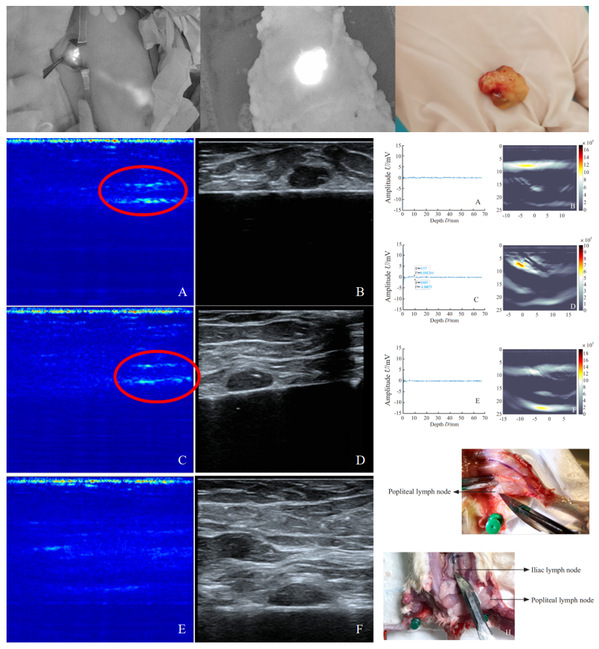

博士生江道淮与山东省肿瘤医院王永胜主任团队硕士生赵家贤合作,在复旦大学附属肿瘤医院主办的中文核心期刊《中国癌症杂志》[9]发表研究论文,提出应用荧光靶向示踪剂吲哚菁绿与利妥昔单抗偶联物(ICG-RIT),搭建了手持式光声信号传感系统及成像系统,探索其探测富集ICG-RIT的淋巴组织的穿透深度,研究了其定位前哨淋巴结的可行性,下一步将进行更系统性的临床实验验证。

图8. 前哨淋巴结的荧光成像,体外光声成像,在体光声传感与成像结果。